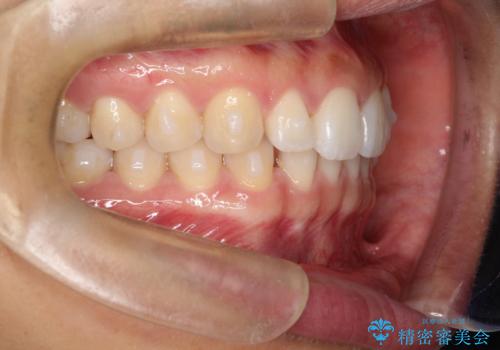

すきっ歯のインビザラインによる目立たない矯正

- すきっ歯を治したいとのことで来院されました。

上下ともに前歯に隙間がありました。

目立たない装置をご希望のためインビザラインで矯正治療を行うこととしました。

使用時間を守っていただけたので、スムーズに治療を終わることができました。